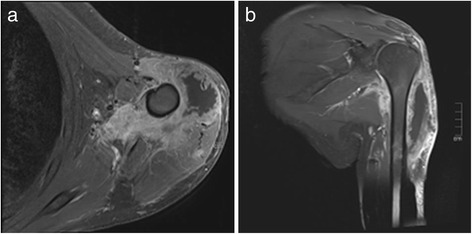

Figure 7.

MR-Imaging of the upper arm in axial (a) and coronal (b) orientation. Both images (fat saturated T1 weighted Images after contrast administration) show a contrast enhanced soft tissue mass in the proximal upper arm with a circular extent around the proximal humeral bone. Extensive soft tissue involvement suggested malignancy but a definitive diagnosis was not possible. On both images a large necrotic central part without contrast enhancement is visible.

The humerus x-ray was not adjuvant making differential diagnosis. Abscess, metastasis and soft tissue tumors could not be distinguished. Therefore a sonography was performed. A typical abscess formation, such as a cavity formation could not be demonstrated, thus a MRI was performed. The MRI was able to illustrate the size and dignity of the mass but a diagnosis still could not be confirmed.

Even with advanced diagnostic tools the radiological appearance was unclear. Conventional methods did not contribute to the diagnosis. The only advantage of the MRI was in accurately describing the dimensions of the tumor. It is a well-known issue that a radiological discrimination of a lesion’s dignity may be limited [27-29]. The most important differential diagnostic discrimination needs to be made between metastastic carcinomas and primary soft tissue sarcoma, since it has serious prognostic and therapeutic implications.